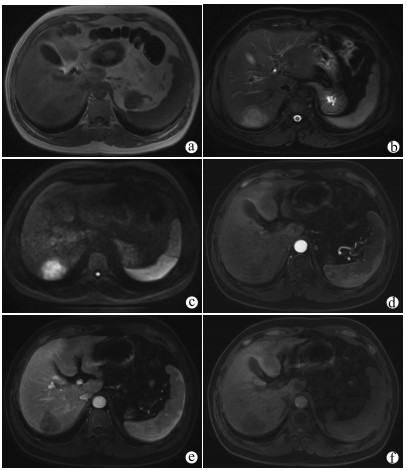

A case of hepatic angiosarcoma with Kasabach-Merritt syndrome

Figures(2)  / Tables(1)